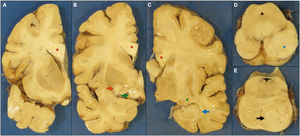

En el estudio del sistema nervioso central se observó un encéfalo de 1.345 g, con leptomeninges lisas y brillantes, sin alteración en el patrón de circunvoluciones. Se encontraron lesiones de aterosclerosis no oclusiva en la arteria basilar, las arterias vertebrales y, en menor medida, en las arterias carótidas internas. En los cortes coronales seriados se observó un marcado engrosamiento del cuerpo calloso, y en menor medida de las cintillas ópticas y de la comisura blanca anterior. En ambos hemisferios la cápsula interna mostraba un ensanchamiento evidente, con una superficie rugosa, con borramiento de la cabeza del caudado, del hipotálamo y del tálamo izquierdos, y del núcleo geniculado lateral derecho. La cabeza del hipocampo derecho aparecía blanquecina y engrosada, nodular. En el tronco del encéfalo, el pedúnculo mesencefálico izquierdo presentaba un engrosamiento nodular, y la hemiprotuberancia homolateral mostró un borramiento de la trama de los núcleos de la base (fig. 4).

Imágenes macroscópicas de secciones coronales del hemisferio izquierdo (A, B), del hemisferio derecho (C), del mesencéfalo (D) y protuberancia (E). Se observa un engrosamiento del cuerpo calloso (A, B y C, asterisco rojo), de la comisura blanca anterior (B, flecha roja) y de las cintillas ópticas (B, flecha verde), afectación del cuerpo geniculado lateral (C, asterisco verde) y lesión nodular en la cabeza del hipocampo posterior derecho (C, flecha azul). Lesión nodular en mesencéfalo (D, asterisco azul) y en hemiprotuberancia izquierda (E, flecha negra).

Histológicamente se observó en estas áreas una lesión densamente celular compuesta por núcleos hipercromáticos de mediano tamaño con frecuentes áreas de necrosis geográfica con seudoempalizada (fig. 5). En el estudio inmunohistoquímico se encontró expresión parcheada de proteína glial en algunas de estas células. No se identificó mutación de IDH1 R132H ni pérdida de expresión de ATRX. Con estos hallazgos morfológicos y este perfil inmunohistoquímico se realizó un diagnóstico de glioblastoma sin mutación de IDH, grado IV de la clasificación de la OMS de 201610, con afectación bilateral asimétrica, extensión desde polo frontal a polo occipital, marcada afectación hipocampal, de cuerpo calloso y mesencéfalo-protuberancial.